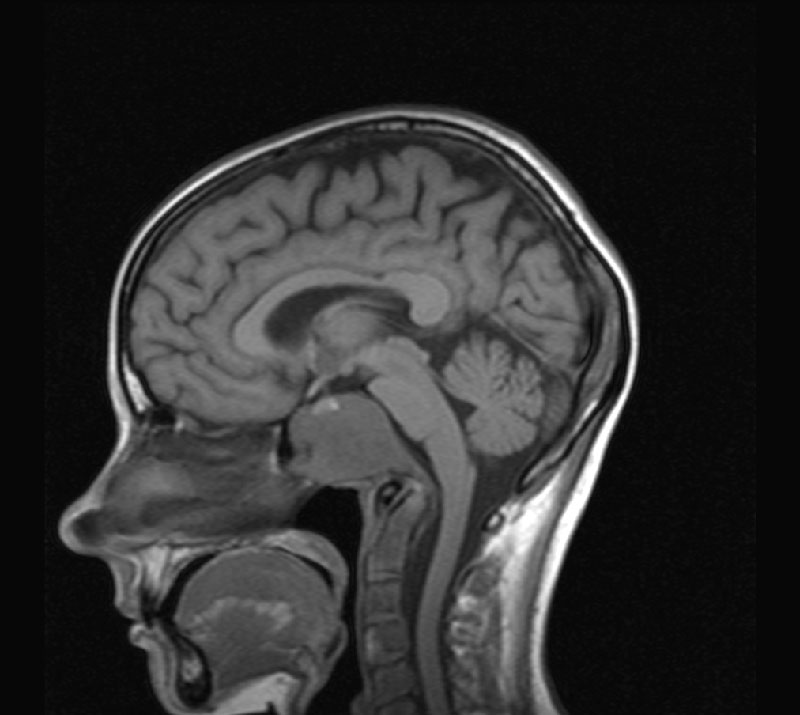

МРТ позвоночника (шейного, грудного и поясничного отделов) позволяет визуализировать структуры позвоночника (кости, нервы, мышцы, связки, диски) и подчас МРТ позволяет обнаружить патологию которую не удается диагностировать с помощью КТ, МСКТ, рентгенографии.

МРТ позвоночника позволяет обнаружить изменения, как в позвоночнике, так и в окружающих тканях (например, инфекции или опухоли).

Примеры исследований